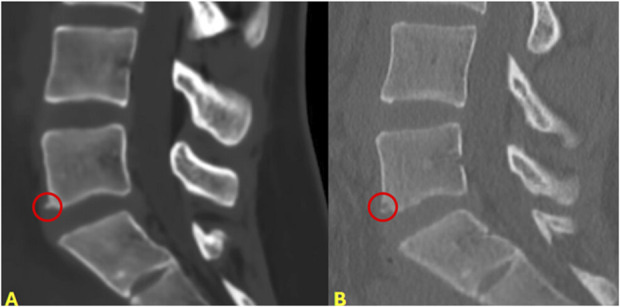

背景:计算机断层扫描(CT)和磁共振成像是常用的影像学研究,用于评估儿童脊柱患者。在尸体研究中,与传统CT (tCT)相比,新型mri生成的合成CT (sCT)图像在准确性上几乎相等。这一最新进展使得在没有有害电离辐射的情况下,骨骼和软组织解剖的可视化成为可能。迄今为止,没有文献报道使用sCT评估儿童脊柱病变。本研究旨在评估sCT在治疗患有各种脊柱疾病的儿童和青少年患者中的临床应用。方法:回顾性分析某第四护理医院2023年10月至2024年9月的小儿脊柱患者。纳入标准包括任何接受sCT脊柱评估的患者。收集患者人口统计学和影像学结果。对于任何在sCT后3个月内接受传统CT (tCT)的患者(n = 10),比较冠状、矢状和轴向序列的骨解剖学测量(每次扫描共10次测量)。还比较了sCT和tCT的官方放射学读数。结果:25例患者行脊柱sCT(2例颈椎,23例腰椎)。适应症包括排除先天性肌性斜颈(2例)、峡部裂(13例)、峡部滑脱(2例)、脊柱侧凸/背痛(4例)、慢性背痛(4例)、腰骶过渡性疼痛(4例)。共进行了176次脊柱骨解剖测量。将tCT与sCT进行比较,62.5%的测量值差异小于0.5 mm, 95.5%的测量值差异小于1 mm, 4.5%的测量值差异大于或等于1 mm。结论:sCT是评估儿童骨性脊柱的一种无辐射的替代成像方式。sCT提供儿童骨骼解剖的三维成像,与tCT相比,大部分在1毫米内。我们相信sCT在儿童和青少年人群中具有重要的临床应用价值,可以在不将患者暴露于辐射和使用单一成像研究的情况下诊断骨骼和软组织病变。证据等级:三级。有关证据水平的完整描述,请参见作者说明。

Results: Twenty-five patients underwent sCT of the spine (2 cervical and 23 lumbar). Indications included rule out congenital cervical anomalies in congenital muscular torticollis (2 patients), spondylolysis (13), spondylolisthesis (2), scoliosis/back pain (4), chronic back pain (4), and back pain with transitional lumbosacral anatomy (4). A total of 176 measurements of spinal osseous anatomy were performed. Comparing tCT with sCT, 62.5% of the measurements differed by less than 0.5 mm, 95.5% by less than 1 mm, and 4.5% differed by 1 mm or more.